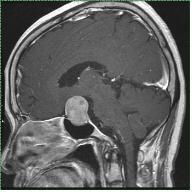

신경초종은 신경세포를 둘러싸고 있는 슈반세포에서 기원한 종양이며, 뇌와 척수에서 모두 발생할 수 있습니다. 이 중 두개강 내에 8번 뇌신경에서 발생하는 신경초종을 청신경초종이라고 합니다. 초기에는 내이도 내에서 발견되고 종양이 커지면서 내이도가 확장되고 다양한 방향으로 자라나 주위 뇌신경, 뇌간, 및 소뇌를 압박하여 여러 신경학적 증상을 유발합니다. 발생 빈도는 원발성 두개강 내 종양의 6~9% 정도이고 두개강 내에 발생하는 신경초종의 90%이상을 차지합니다. 주로 30세 이후의 성인에서 발생하며 여성이 남성보다 2배 정도 발생률이 높다고 알려져 있습니다. 20세 미만에서는 제2형 신경섬유종증 환자에서 양측성으로 주로 발생합니다. 청신경초종은 95% 이상이 편측성으로 발생하고, 이 경우 비유전적으로 발생합니다. 약 5%이하에서 양측성으로 발생하는 경우가 있는데 이는 제2형 신경섬유종증과 연관되어 있을 가능성이 높습니다. 제2형의 신경섬유종증은 제1형 신경섬유종증에 비해 아주 드물게 발생하는데 양측에 발생한 청신경초종 또는 청신경초종이 동반된 다발성 뇌척수 수막종, 성상 세포종, 상의 세포종 등이 주로 발생하는 것으로 알려져 있습니다.